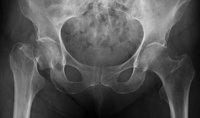

Cerca de tres millones de personas padecen osteoporosis en España, una enfermedad que reduce la densidad y calidad de los huesos, debilitando el esqueleto y aumentando el riesgo de fractura. Las mujeres son las más afectadas por esta patología y se calcula que dos de cada tres la sufrirán después de la menopausia.

La osteoporosis no presenta síntomas en sus etapas iniciales y, a menudo, es la primera fractura la que lleva a descubrirla, las cual suele afectar a la columna vertebral, las muñecas, la cadera, la pelvis y el húmero.